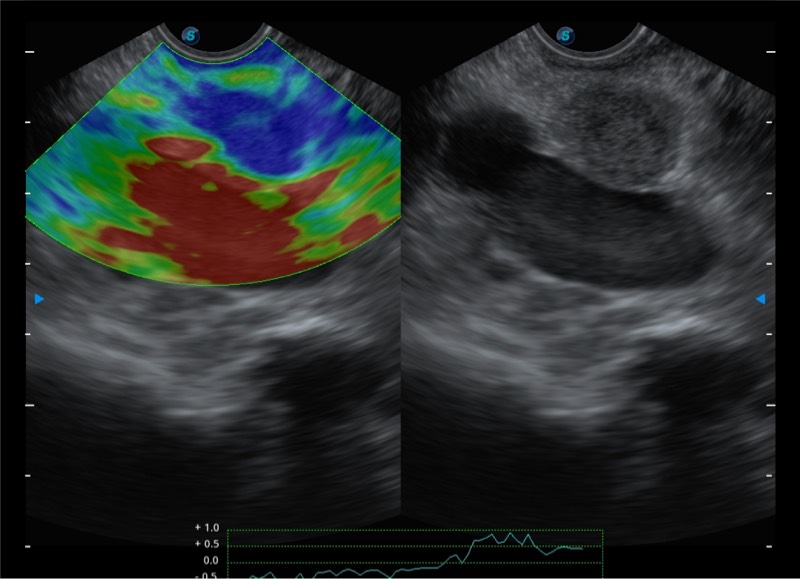

基于二十年的超声技术积累,玖鼎集团提供了最新一代的独立超声主机,在提供高质量图像的同时满足多学科使用。具备常见多普勒技术并提供弹性成像、声学造影等高端影像技术。新一代传感器具有更强的抗干扰能力并减少图像伪影。

4-12MHZ宽频输出